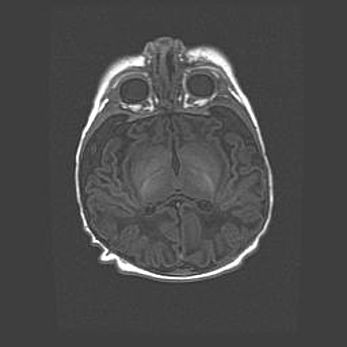

Неполная лизэнцефалия (пахигирия). Открытая гидроцефалия.

Возраст: 17 дней

Вес: 3110 г

Пол: мужской

Окружность головы: 33,5 см

Срок гестации: 35-36 недель

Лизэнцефалия—недоразвитие корковой пластинки и мозговых извилин в результате нарушения миграции нейронов коры. Поверхность мозговых полушарий гладкая. Микроскопически выявляется отсутствие нормальных слоев коры и скопление групп нейронов в подкорковом белом веществе.

Пахигирия—уменьшение числа вторичных извилин. В пораженном полушарии нервные клетки образуют толстый недифференцированный слой с неправильно расположенными нервными волокнами и группами гетеротопных клеток. Нервные клетки незрелые. Белое вещество истончено. При этом нередко аномально развит корково-спинномозговой путь.